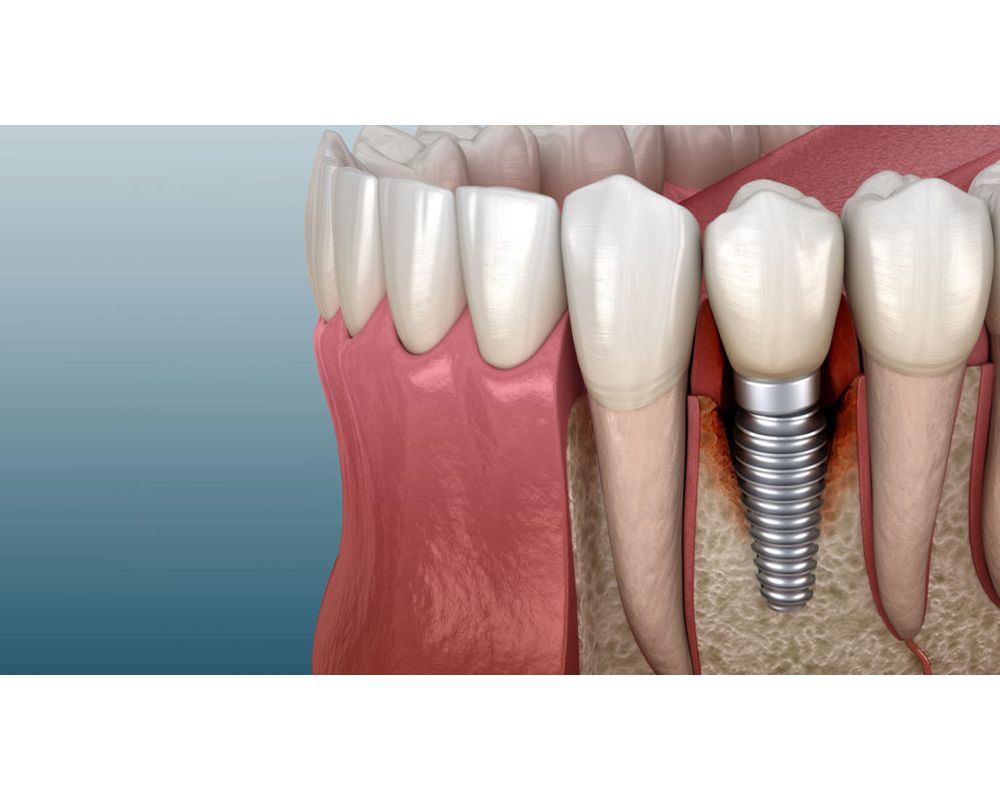

What is Periimplantitis and What Do I Do About It? Bone Loss Around Dental Implant Complication The possible treatment options for implant failure include the replacement of a faulty implant right away with one with a larger. Dental implants are an effective way of replacing lost or damaged adult teeth. While dental implants are increasingly becoming the choice of replacement for missing teeth, the impediments associated with them are. If you’re scheduled to have dental implant. Dental Implant Complication.